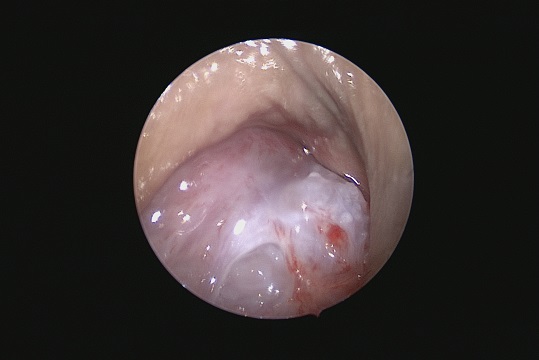

Neurovascular Surgery

Management of aneurysms, arteriovenous malformations, and stroke.